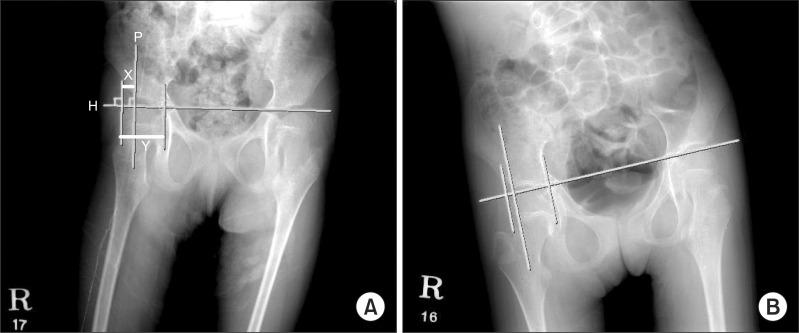

We researched 34 severely disabled patients who had used a custom molded fitting chair continuously for more than a year. There were 27 cerebral palsy patients and 7 patients with other kinds of diseases that affect the brain such as chromosomal disease or metabolic disease. By radiographic studies, Cobb's angle, the femoral neck-shaft angle of the femur, and Reimers migration percentage were measured. The indices are analyzed before and after application.

The average period of application was 24 months. There was a significant reduction in the angles of femur neck-shaft, 163.4 degree before and 158.2 degree after the use of the chair (p<0.05), and 23 of 34 had demonstrated a reduced angle. Cobb's angle and Reimers migration percentage increased but the difference of pre- and post-chair status was not statistically significant. Seventeen of 33 children showed reduced Cobb's angle. Also, 19 of 37 showed a reduced degree of dislocation of the hip joints.

我们研究了34名连续使用定制塑形适配椅超过一年的重度残疾患者。其中有27名脑瘫患者和7名患有其他影响大脑的疾病(如染色体疾病或代谢疾病)的患者。通过影像学研究,测量了 Cobb角、股骨颈干角和赖默斯移位百分比。对应用前后的指标进行分析。

平均应用时间为24个月。使用椅子后,股骨颈干角有显著减小,使用前为163.4度,使用后为158.2度(p<0.05),34名患者中有23名角度减小。Cobb角和赖默斯移位百分比增加,但使用椅子前后的差异无统计学意义。33名儿童中有17名Cobb角减小。此外,37名中有19名髋关节脱位程度减小。